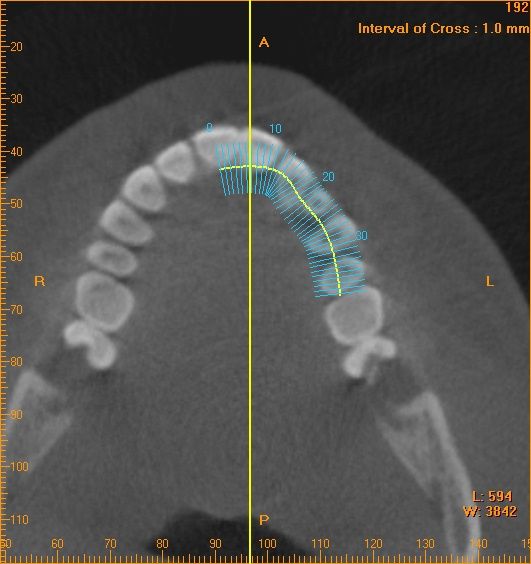

さらにCTを撮影して それぞれの根の状態をチェックします

ここでは省略しますが、顎の立体像を構築して 歯の関係と顎の関係もチェックしております